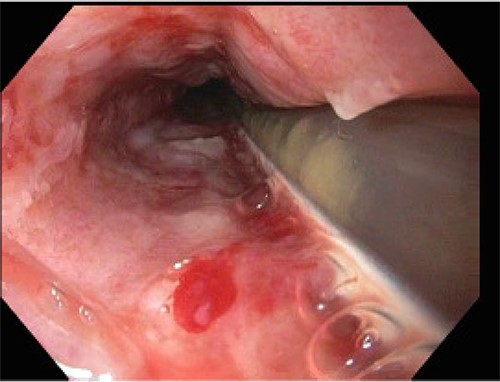

On POD 15, the patient was noted to have bloody output from the orogastric tube and esophagogastroduodenoscopy was performed. Diffuse esophageal and gastric ulcerations were noted, consistent with HSV esophagitis (Figs 1 and 2). The patient began improving clinically. Vasopressors were discontinued and patient was extubated the following morning. She was transferred out of the ICU on POD 28 with improvement of renal function and discontinuation of dialysis. Patient was discharged on POD 39.

HSV1 infections usually cause ulcerated lesions. HSV viremia has been reported in up to 25% of immunocompetent patients with primary HSV infections [5]. Overall, the incidence of HSV1 reactivation in critically ill patients with septic shock ranges from 32 to 68% [6]. HSV1 esophagitis is a well-known complication as the esophagus is the most commonly involved visceral organ. HSV esophagitis is usually found in patients with acquired immunodeficiency syndrome, malignancies, those receiving immunosuppressive therapy or terminally ill [7]. There is no clearly defining link between preoperative hydrocortisone use over a short period of time and significant immunosuppression. Currently, there is no consensus on the risk of reactivation of cutaneous HSV1 progressing into disseminated viremia. The possible reasons for our patient include immunosuppression, spinal surgery in an obese patient, the development of ARDS or the preceding fungemia. ACS-NSQIP data from 2011 to 2014 identified that 3.7% of patients who underwent elective posterior lumbar fusion were on chronic glucocorticoids [8]. As previously mentioned, 67% of global population is estimated to be affected by HSV. This case demonstrates that the possibility of disseminated viral infection must be considered even after elective spinal cases.